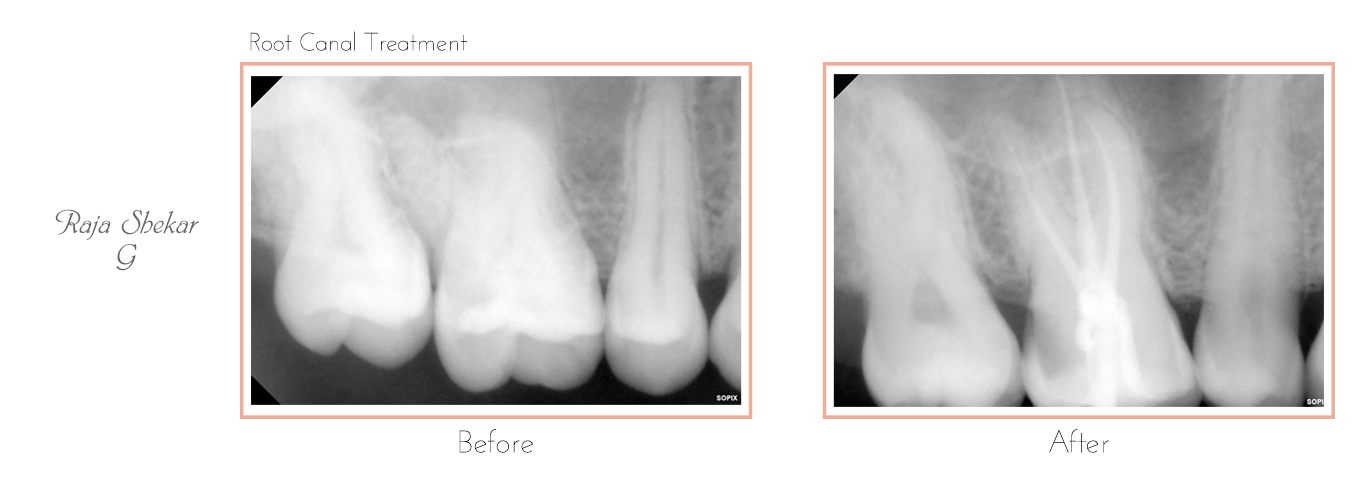

Root Canal Treatment

The very first step involves an X-ray which is taken to determine the extent and approach to infection. If required local anesthesia is administered before starting the treatment.

Clean and disinfected canals are then sealed and filled with an inert rubber-like filling material known as Gutta-Percha.